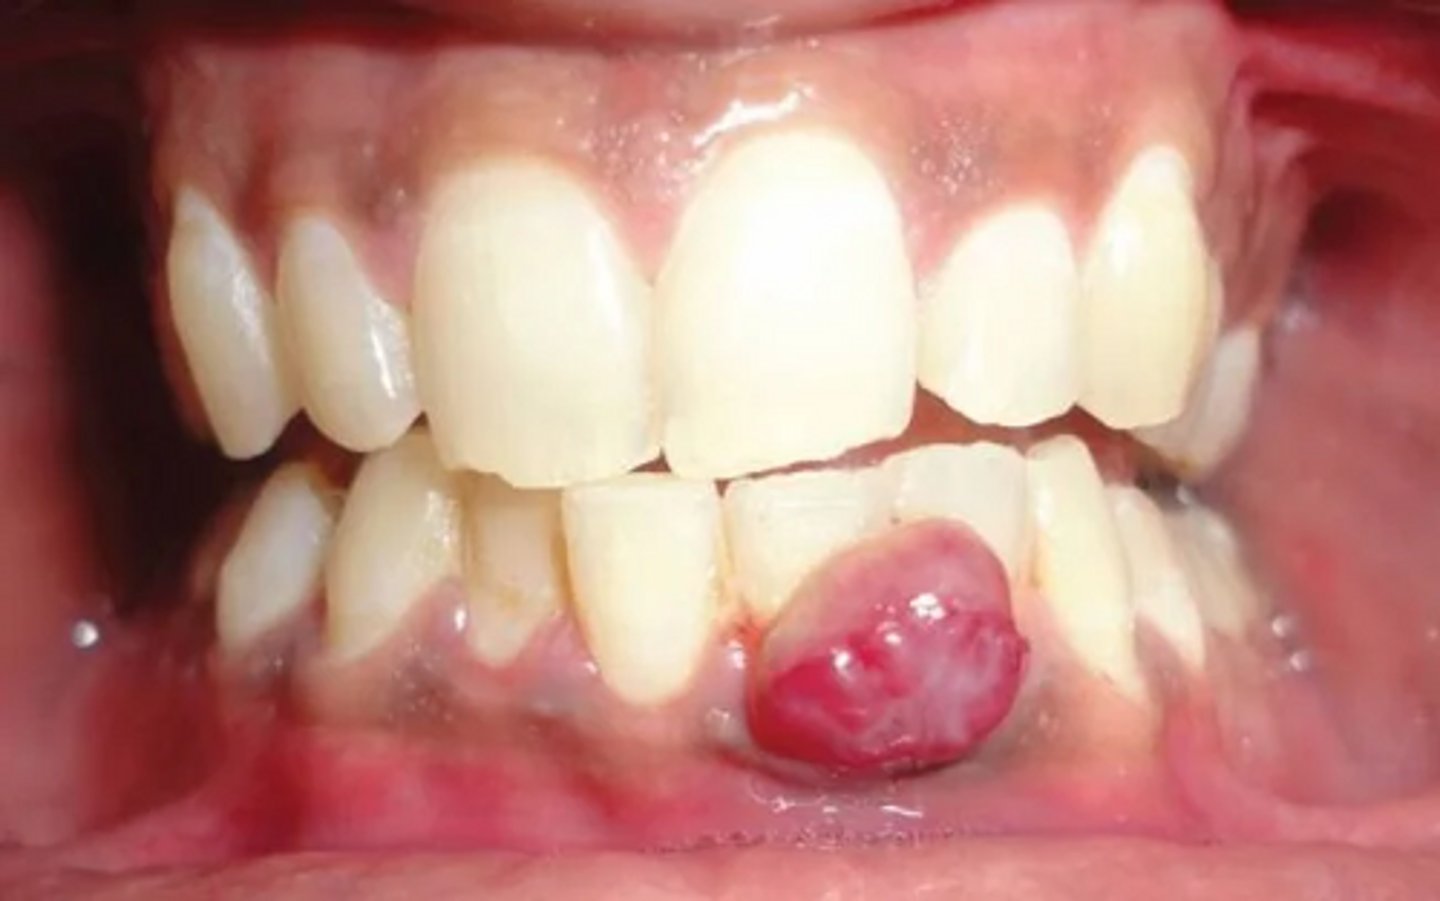

A lesion is described as a benign, solitary vascular growth that represents an exuberant tissue response to local irritation or trauma.

pyogenic granuloma

A patient presents with a pyogenic granuloma on the gingiva. What is the most appropriate treatment?

surgical excision and removal of local irritants

Which of the following is NOT a characteristic of pyogenic granuloma?

contains purulent exudate